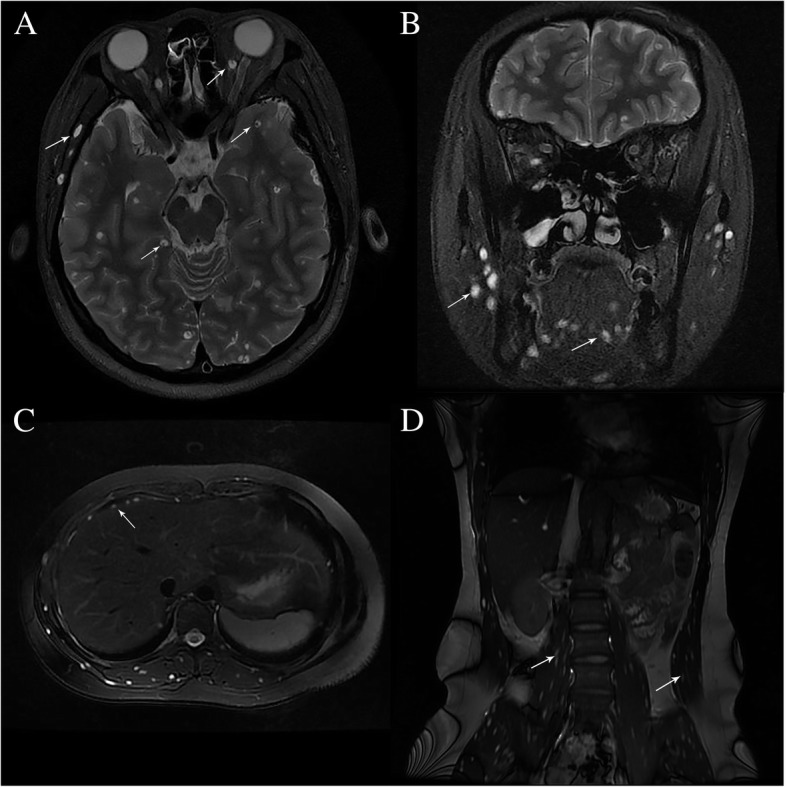

Magnetic resonance imaging (MRI) with Gd-DTPA as the contrast agent was performed. MRI of the orbits and brain showed well-defined ring-enhancing cystic lesions with eccentric scolexes in the extraocular muscles, brain parenchyma (Fig. 2a), tongue, face, neck muscles, and cutaneous tissues (Fig. 2b). Abdominal MRI revealed round hyperintense lesions in the diaphragm, abdominal muscles, erector spinae, and psoas magnus muscles in T2-weighted images (T2WI) with an identifiable hypointense nidus in T1-weighted images (T1WI) and T2WI. Cystic lesions were found to be scattered around muscle tissues of the whole body (Fig. 2c and d).

Fig. 2.

MRI of the brain, orbit, and body. Fat-suppressed T2-weighted axial and coronal images of brain and abdomen showed numerous well-defined hyperintense lesions with eccentric scolex involving the (a) left temporal lobe, left orbital muscle, right diaphragm, right occipital lobe, (b) masseter, tongue muscles, (c) erector spinae, and (d) psoas magnus muscles